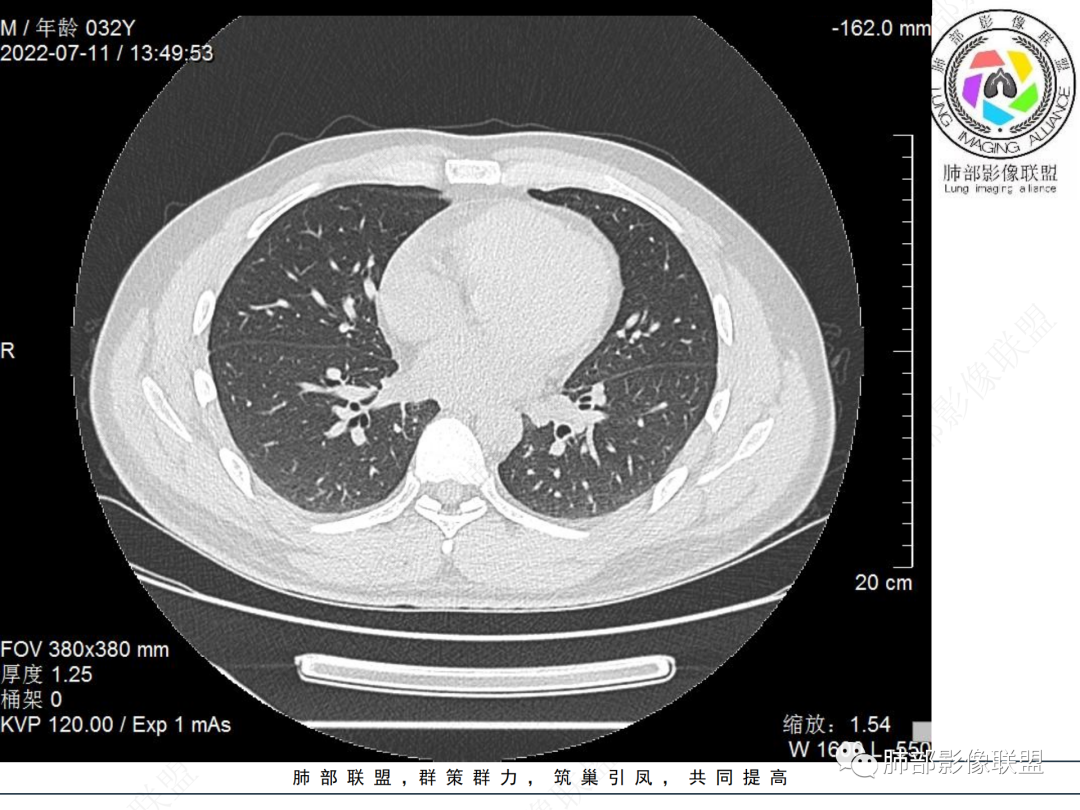

左肺下叶后基底段开口处结节,边缘光滑清楚,没有增强扫描,年轻男性患者痰血三天,考虑1.良性病变:腺瘤、错构瘤、平滑肌瘤

左肺下叶外后基底段气管内见结节状影,边缘部分清晰。考虑错构瘤,待排恶性病变。

青年男性,左肺下叶后基底段支气管开口软组织结节,边缘光整,气管镜提示质软,易出血,考虑类癌

左肺下叶后基底段开口处腔内见壁结节,花生米样,宽基底,补充增强及矢状位重建,确定我无向壁外突破浸润生长,另见强化的特点,临床触之易出血,类Ca可能性大。

年轻男性,咳血,左肺下叶后基底段支气管腔内结节,边缘光滑,首先考虑青年三件套,类癌大于粘液表皮样癌,支气管镜质软,触之易出血,鉴别血管瘤,平滑肌瘤

左肺下叶后基底段开口部结节,密度较均匀一致,边缘较光整,目测密度偏低,支气管镜示:质软、触之易出血,考虑恶性,类癌。

IMT常表现为边缘清晰的周围型结节或肿块,一般体积相对较大。大约10%-20%发生于支气管及气管腔内,表现为中央型病变,一般为单发。IMT胸部CT显示90%为单发结节或肿块。

多发生主、叶及段支气管,支气管腔内/外生长的结节或肿块,多靠近气道分叉处。常合并神经内分泌症状。30%可伴有钙化,多点状或弥漫性钙化。增强后明显强化。